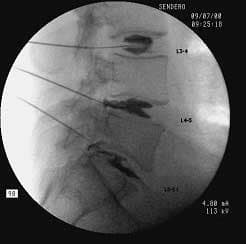

Discography enables the physician to detect the pain-causing disc. The suspected disc along with a control disc(s) are injected with x-ray contrast to determine whether the usual chronic pain is reproduced. A follow up CT scan is done after the procedure to visualize the contrast in the disc, looking for tears and leaks. Once the offending disc is identified, IDET or a surgical option is considered. The IDET procedure involves placing a flexible electrode into the painful disc annulus and heating it to a high temperature to coagulate adjacent tissue. Simultaneously, the pain sensing nerve fibers within the disc are destroyed by the heat, providing pain relief.